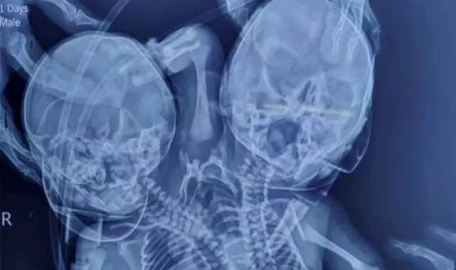

Dünyada çok az rastlanan bir olay 28 Mart tarihinde Hindistan’da yaşandı. Disefalik parapagus olarak bilinen halk dilinde yapışık ikizler olarak doğan bebekler iki kalp, iki kafa ve üç kollu olarak doğdu. Hastanede doktorlar tarafından mucize bebek olarak adlandırılan ikizler, anne ve babaları tarafından hoş karşılanmadı.

Hindistan'ın Madhya Pradesh eyaletinin Ratlam kentinde dünyaya gelen iki kalbi, üç kolu ve iki kafası olan bebek görenleri şaşkına uğrattı.

Disefalik parapagus olarak bilinen bu durum genelde ölü doğumla sonuçlanır. Bebeklerin anne ve babası doğuma kadar ikiz bebekleri olacaklarını sanıyorlardı. 18 aydır evli olan çift durumdan hoşnut olmadıklarını dile getirdi. Hastanede yaşam mücadelesi veren bebekler doktorlar tarafından ‘mucize bebekler’ olarak adlandırıldı.

Doktorlardan biri olan Dr. Lahoti, "Bu tür vakalar çok nadir görülür ve bebeklerin durumu özellikle ilk günlerde belirsizliğini korur. Bu nedenle onları müşahede altında tutuyoruz. Hasta üzerinde herhangi bir ameliyat planlamadık." dedi. İki başlı bebek olayı en son yine Hindistan’da 2019 yılında yaşanmıştı.